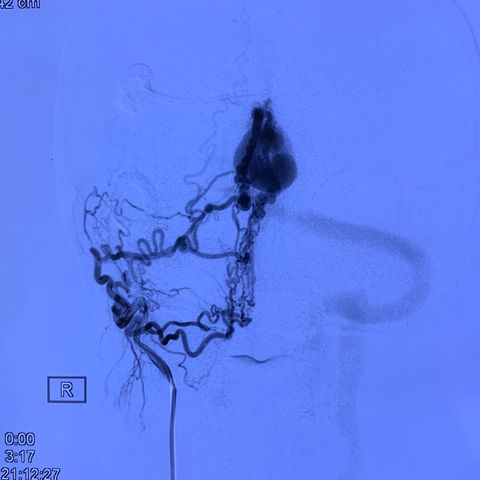

王瑶,女,38岁,动静脉畸形